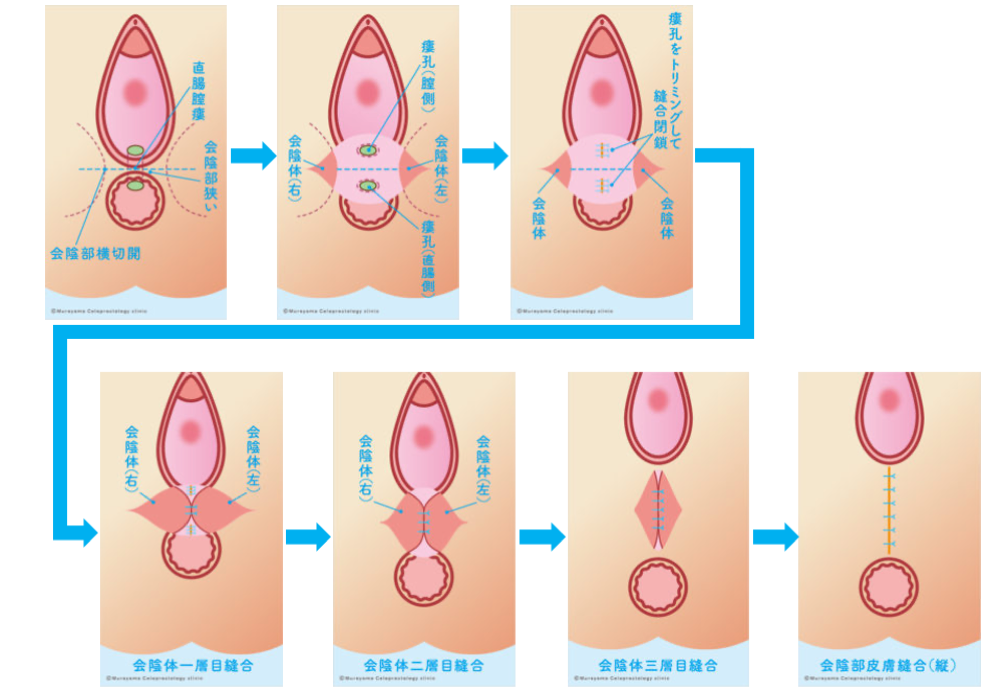

女性の肛門疾患 大阪市住吉区あびこ駅前の肛門外科 むらやま大腸肛門クリニック

女性の肛門疾患 大阪市住吉区あびこ駅前の肛門外科 むらやま大腸肛門クリニック

女性の肛門疾患 大阪市住吉区あびこ駅前の肛門外科 むらやま大腸肛門クリニック